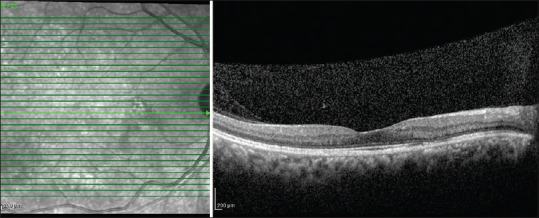

中枢性浆液性脉络膜视网膜病变(CSCR)的发生是由于脉络膜毛细血管的高渗透性,与视网膜色素上皮(RPE)功能障碍一起,导致浆液性神经感觉视网膜脱离。限定脉络膜血管瘤也以黄斑浆液性神经感觉脱离为特征,引起RPE退行性改变,很少模仿CSCR。在此,我们报告一例中年患者的CSCR,表现为脉络膜肿块病变,表现为孤立的脉络膜升高,视网膜下有液体和脉络膜后积液,在眼底荧光血管造影引导的病灶激光后显示液体完全溶解。

Central serous chorioretinopathy (CSCR) occurs due to hyper-permeable choroidal capillaries, which, along with retinal pigment epithelium (RPE) dysfunction, causes a serous neurosensory retinal detachment. Circumscribed choroidal hemangiomas are also characterized by serous neurosensory detachment of the macula and cause degenerative changes to the RPE, rarely mimicking CSCR. Here, we present a case of CSCR in a middle-aged patient mimicking as a choroidal mass lesion who presented as a solitary choroidal elevation with subretinal fluid and posterior choroidal loculation of fluid and showed complete resolution of fluid after fundus fluorescence angiography-guided focal laser.